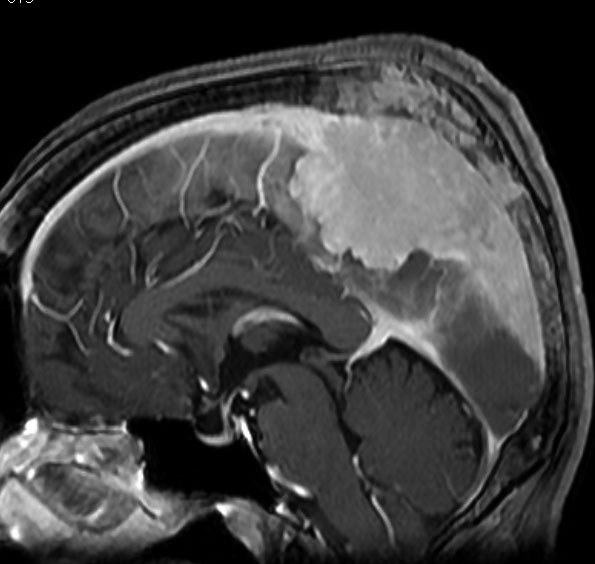

上矢状洞髄膜腫 superior sagittal sinus meningioma

また別な例です。1986年13歳の時に2度の開頭手術を受けましたが,全摘出できずにそのまま経過観察されました。

左の画像は1997年の術前のものです。これを2回に分けて全摘出しました。上矢状洞はやはり冠状縫合のあたりから静脈洞交会まで摘出しました。その下の大脳鎌も全て摘出したので,直静脈洞の上壁を開けることになり,直静脈洞からの激しい出血があり縫合して直静脈洞形成をするのが大変でした。手術後16年が経過しますが再発していませんし,社会人として普通に暮らせています。

この例が教えてくれることは,上矢状静脈洞は全長にわたり切除してしまっても,神経脱落症状を出さないで普通に生きて行かれるということです。